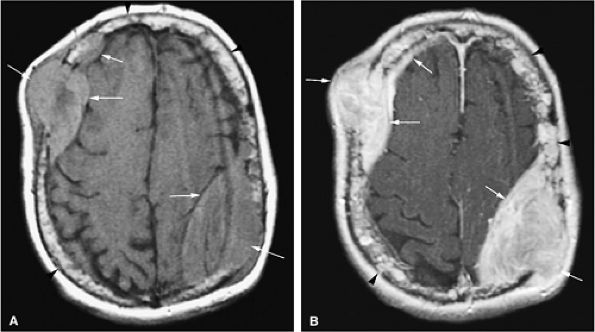

FIGURE 13.57 ● Extensive bone marrow replacement of the skull secondary to metastatic renal cell cancer (arrowheads). Large focal lesions with intracranial extension are present (arrows). (A) Axial proton density-weighted image shows expansion of the marrow cavity and metastatic deposits that demonstrate intermediate signal intensity. (B) Extensive enhancement of metastatic disease is seen on an axial fat-suppressed T1-weighted image following the intravenous administration of gadolinium.